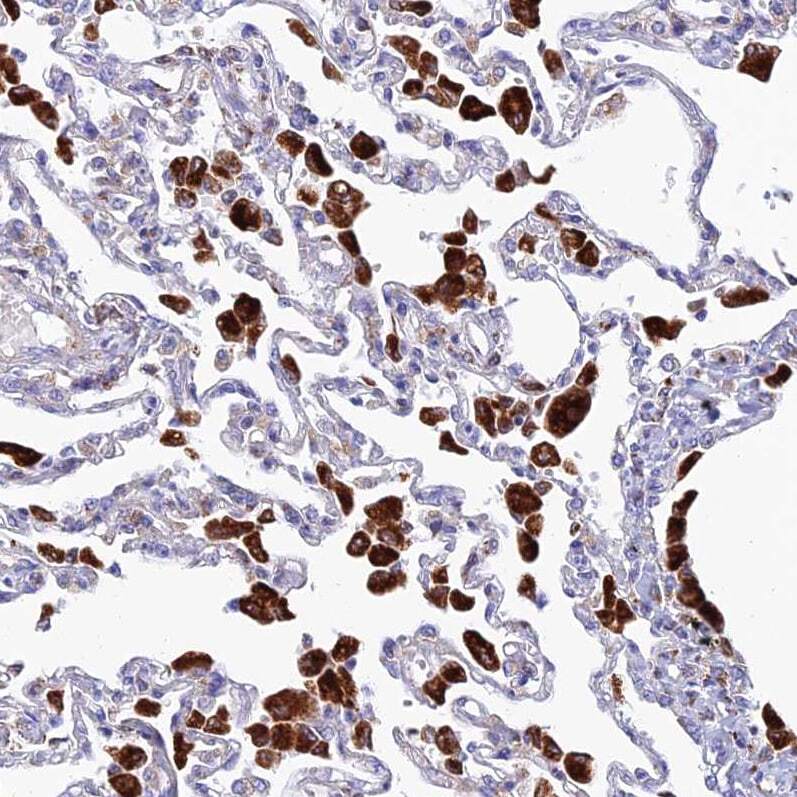

- Immunohistochemical analysis of SPNS1 in human lung using SPNS1 Polyclonal Antibody (Product # PA5-59813) shows strong granular cytoplasmic positivity in macrophages.